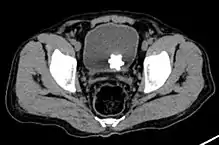

Large jackstone in the bladder of a 60-year-old man. Stone was removed by open cystolithotomy

Jackstone calculus

Jackstone calculi are rare bladder stones that have an appearance resembling toy jacks. They are almost always composed of calcium oxalate dihydrate and consist of a dense central core and radiating spicules. They are typically light brown with dark patches and are usually formed in the urinary bladder and rarely in the upper urinary tract. Their appearance on plain radiographs and computed tomography in human patients is usually easily recognizable. Jackstones often must be removed via cystolithotomy.[10]